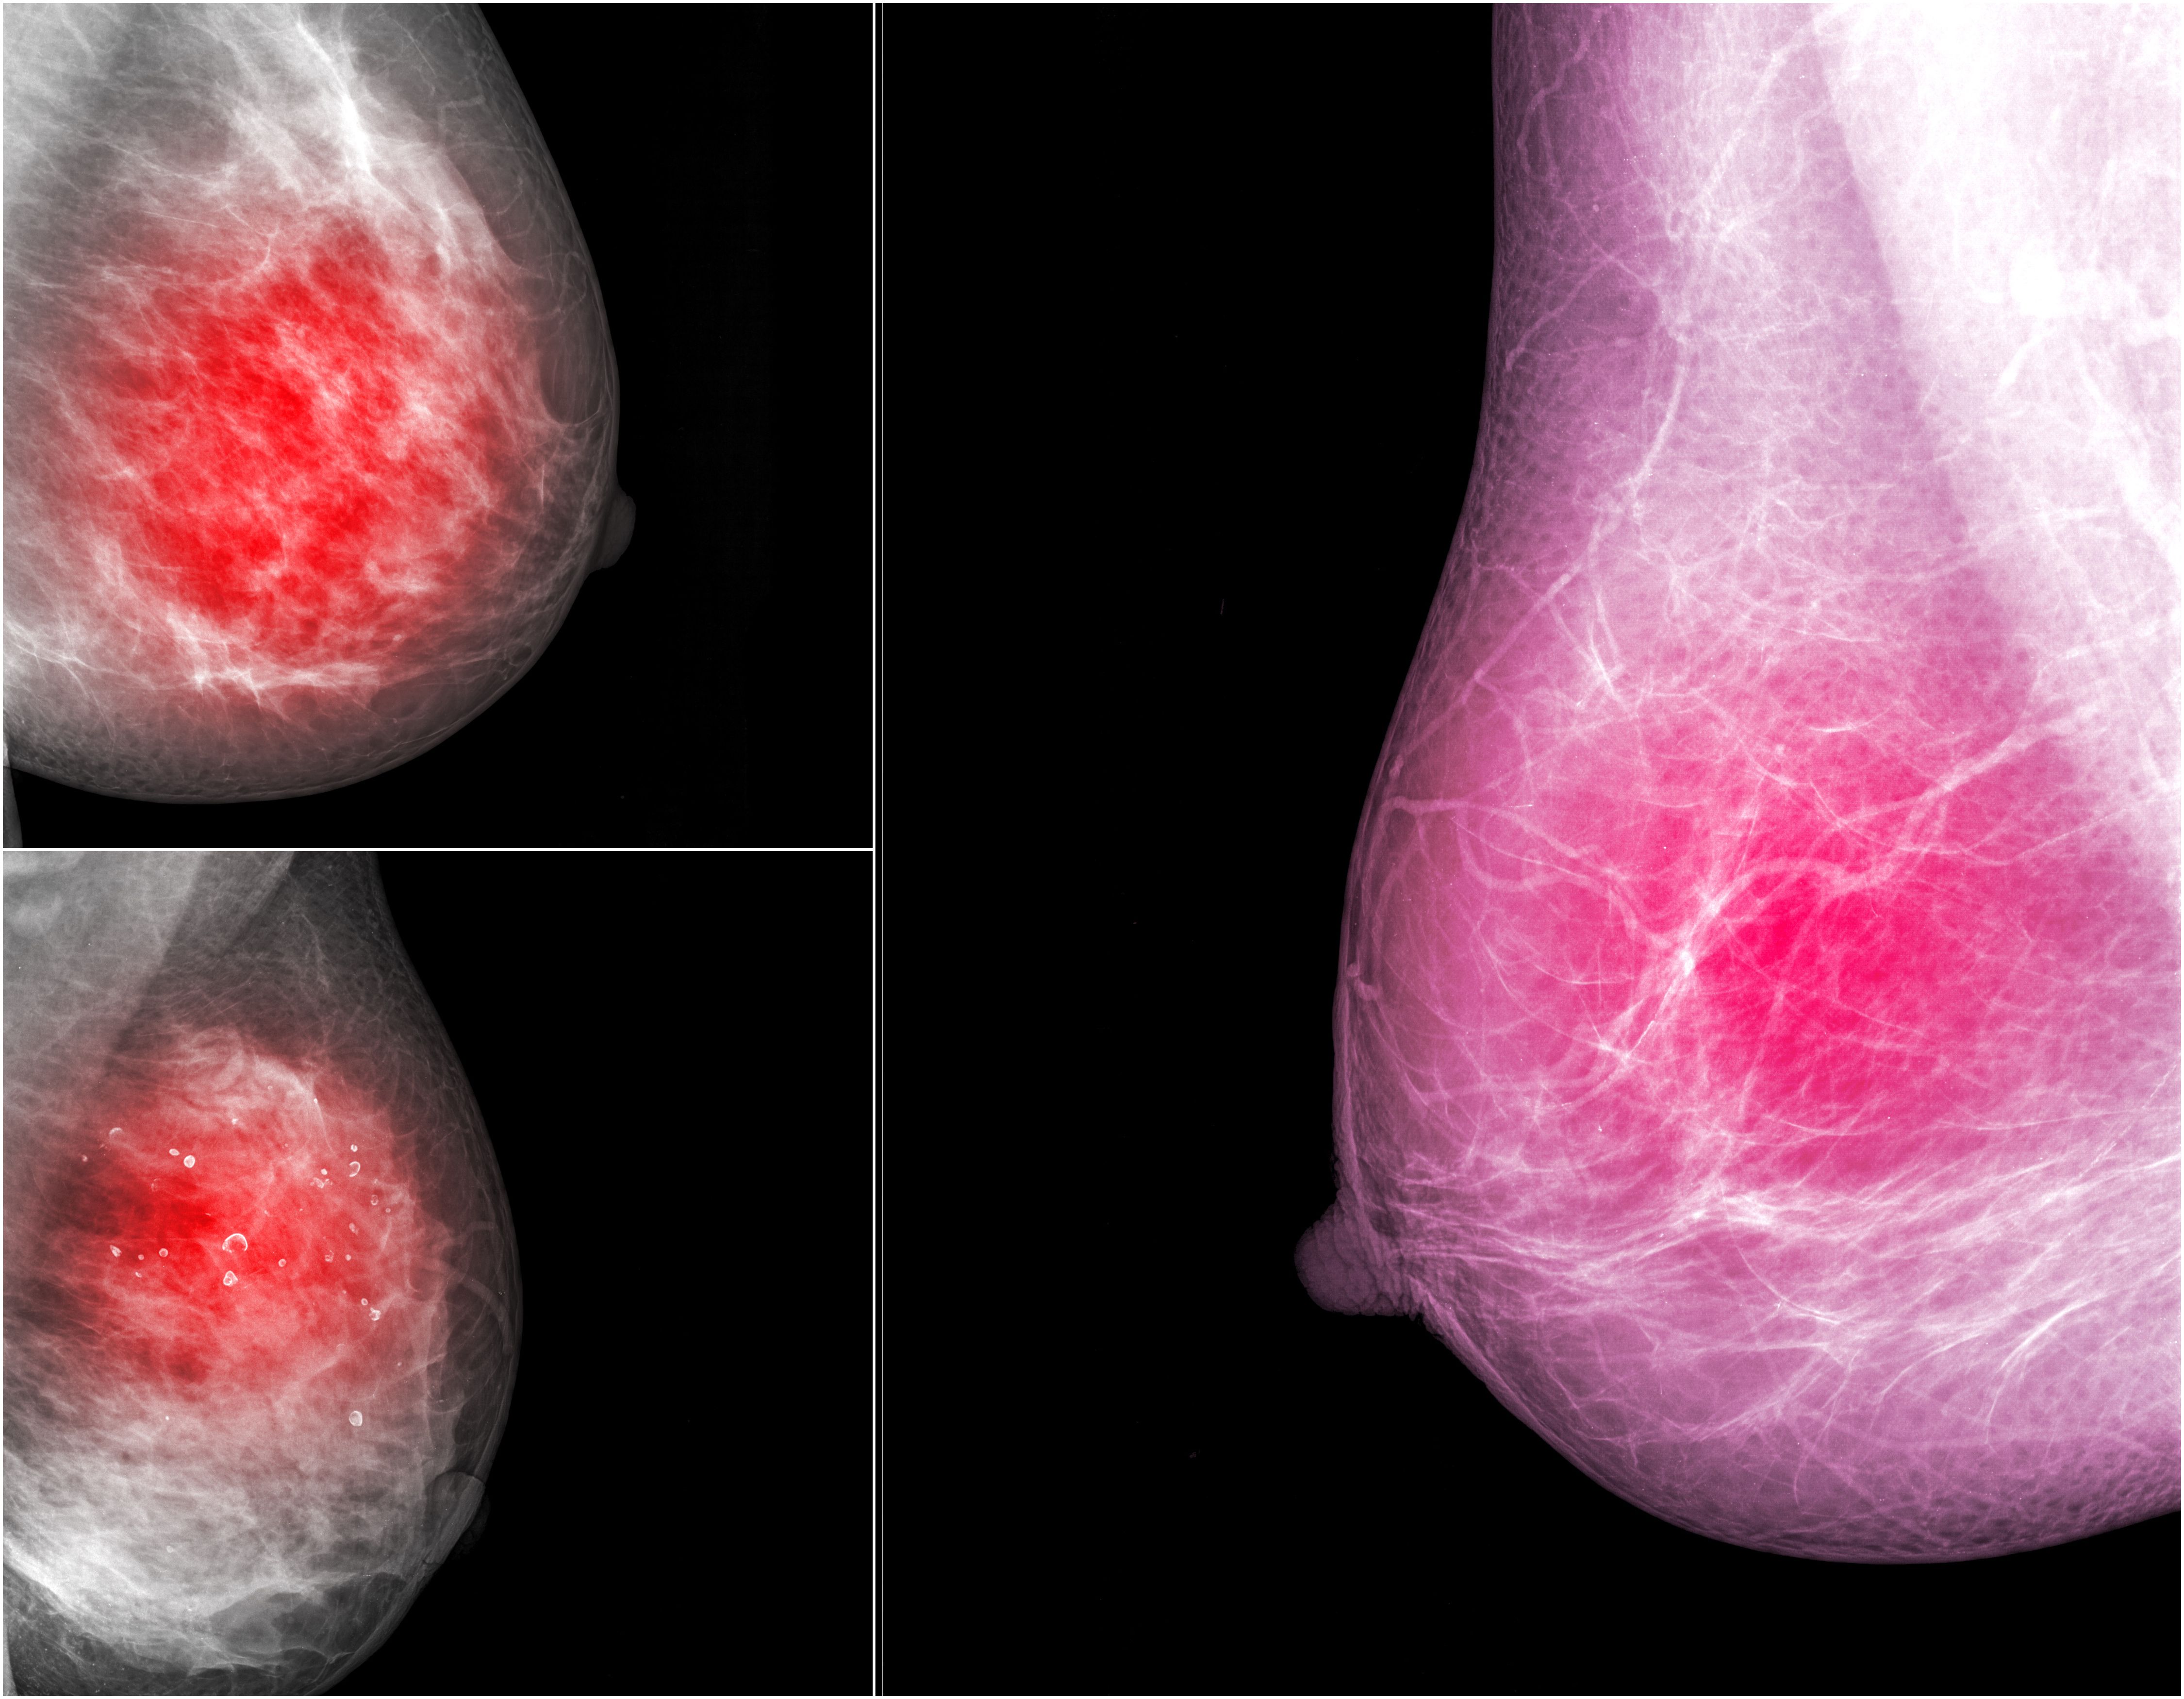

Can Contrast-Enhanced Mammography Provide a Viable Option for Breast Cancer Detection?

CEM performance showed no significant difference between women with or without breast implants, and it produced very few complications.

Findings show contrast-enhanced mammography is an acceptable option for women who may not have access to MRI or who cannot undergo the exam.